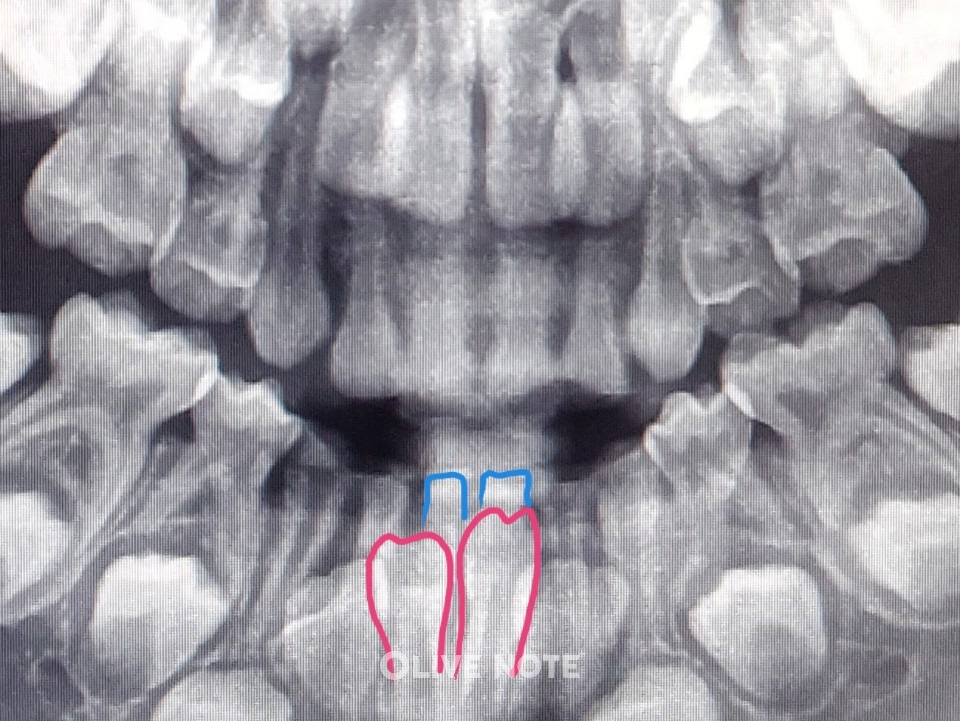

2319_6302_73.jpg 아이의 치아 엑스레이 사진이에요. 영구치(빨간색)가 충분히 올라 왔다는 게 확인되면 유치(파란색)를 뽑아요.

A. 아니요. 이가 흔들린다고 무조건 발치하지 않습니다. 치아 엑스레이를 찍어 영구치가 충분히 올라왔는지 확인해야 합니다. 너무 일찍 유치를 빼면 옆의 이가 기울어질 수 있고 밥을 먹을 때 불편하기 때문이죠.